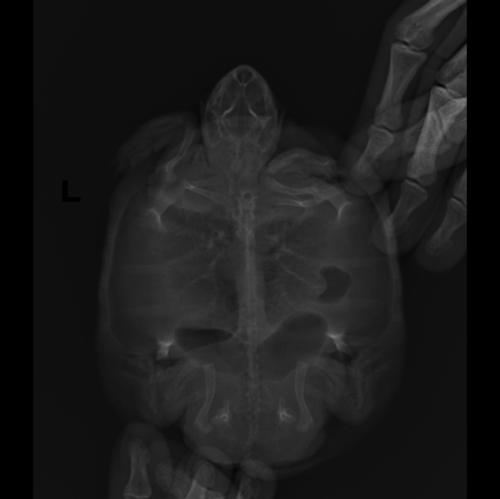

Анастасия- Ваше имя: Анастасия Локация: Ереван Опубликовано: 18 января 2022 Автор Опубликовано: 18 января 2022 Вот такой у нас сегодняшний рентген, врач сказала продолжать антибиотик, прийти на повторный анализ крови а вот это рентген от 4 января перед курсом антибиотиков и уколами Элеовита:

Консультанты moth Ваше имя: Мария Локация: Москва Опубликовано: 18 января 2022 Консультанты Опубликовано: 18 января 2022 @Анастасия- по лёгким тут явно лучше на сколько я могу читать снимки - по-моему там есть скопление газов, что и могло приводить к тому, что Вы описывали. Врач ничего не говорила про это?

Анастасия- Ваше имя: Анастасия Локация: Ереван Опубликовано: 18 января 2022 Автор Опубликовано: 18 января 2022 @moth врач сказала, что в кишечнике много газов, пока ждать что будет дальше, и что кусочков инородных больше не видно. Сегодня делали у врача укол Элеовита, а вечером уже я делала антибиотик, и черепашка обмочилась очень желтым, такого яркого раньше не было - наверное из-за витаминов? Сегодня черепашка довольно подвижная, то плавает, то на островке сидит, но кушать пока отказывается

Консультанты moth Ваше имя: Мария Локация: Москва Опубликовано: 18 января 2022 Консультанты Опубликовано: 18 января 2022 @Анастасия- да, цвет из-за витаминов. Ну будем надеяться, что всё будет хорошо. Газы сильно сдавливают лёгкие и другие органы, черепахе больно и не комфортно, поэтому так себя вела.